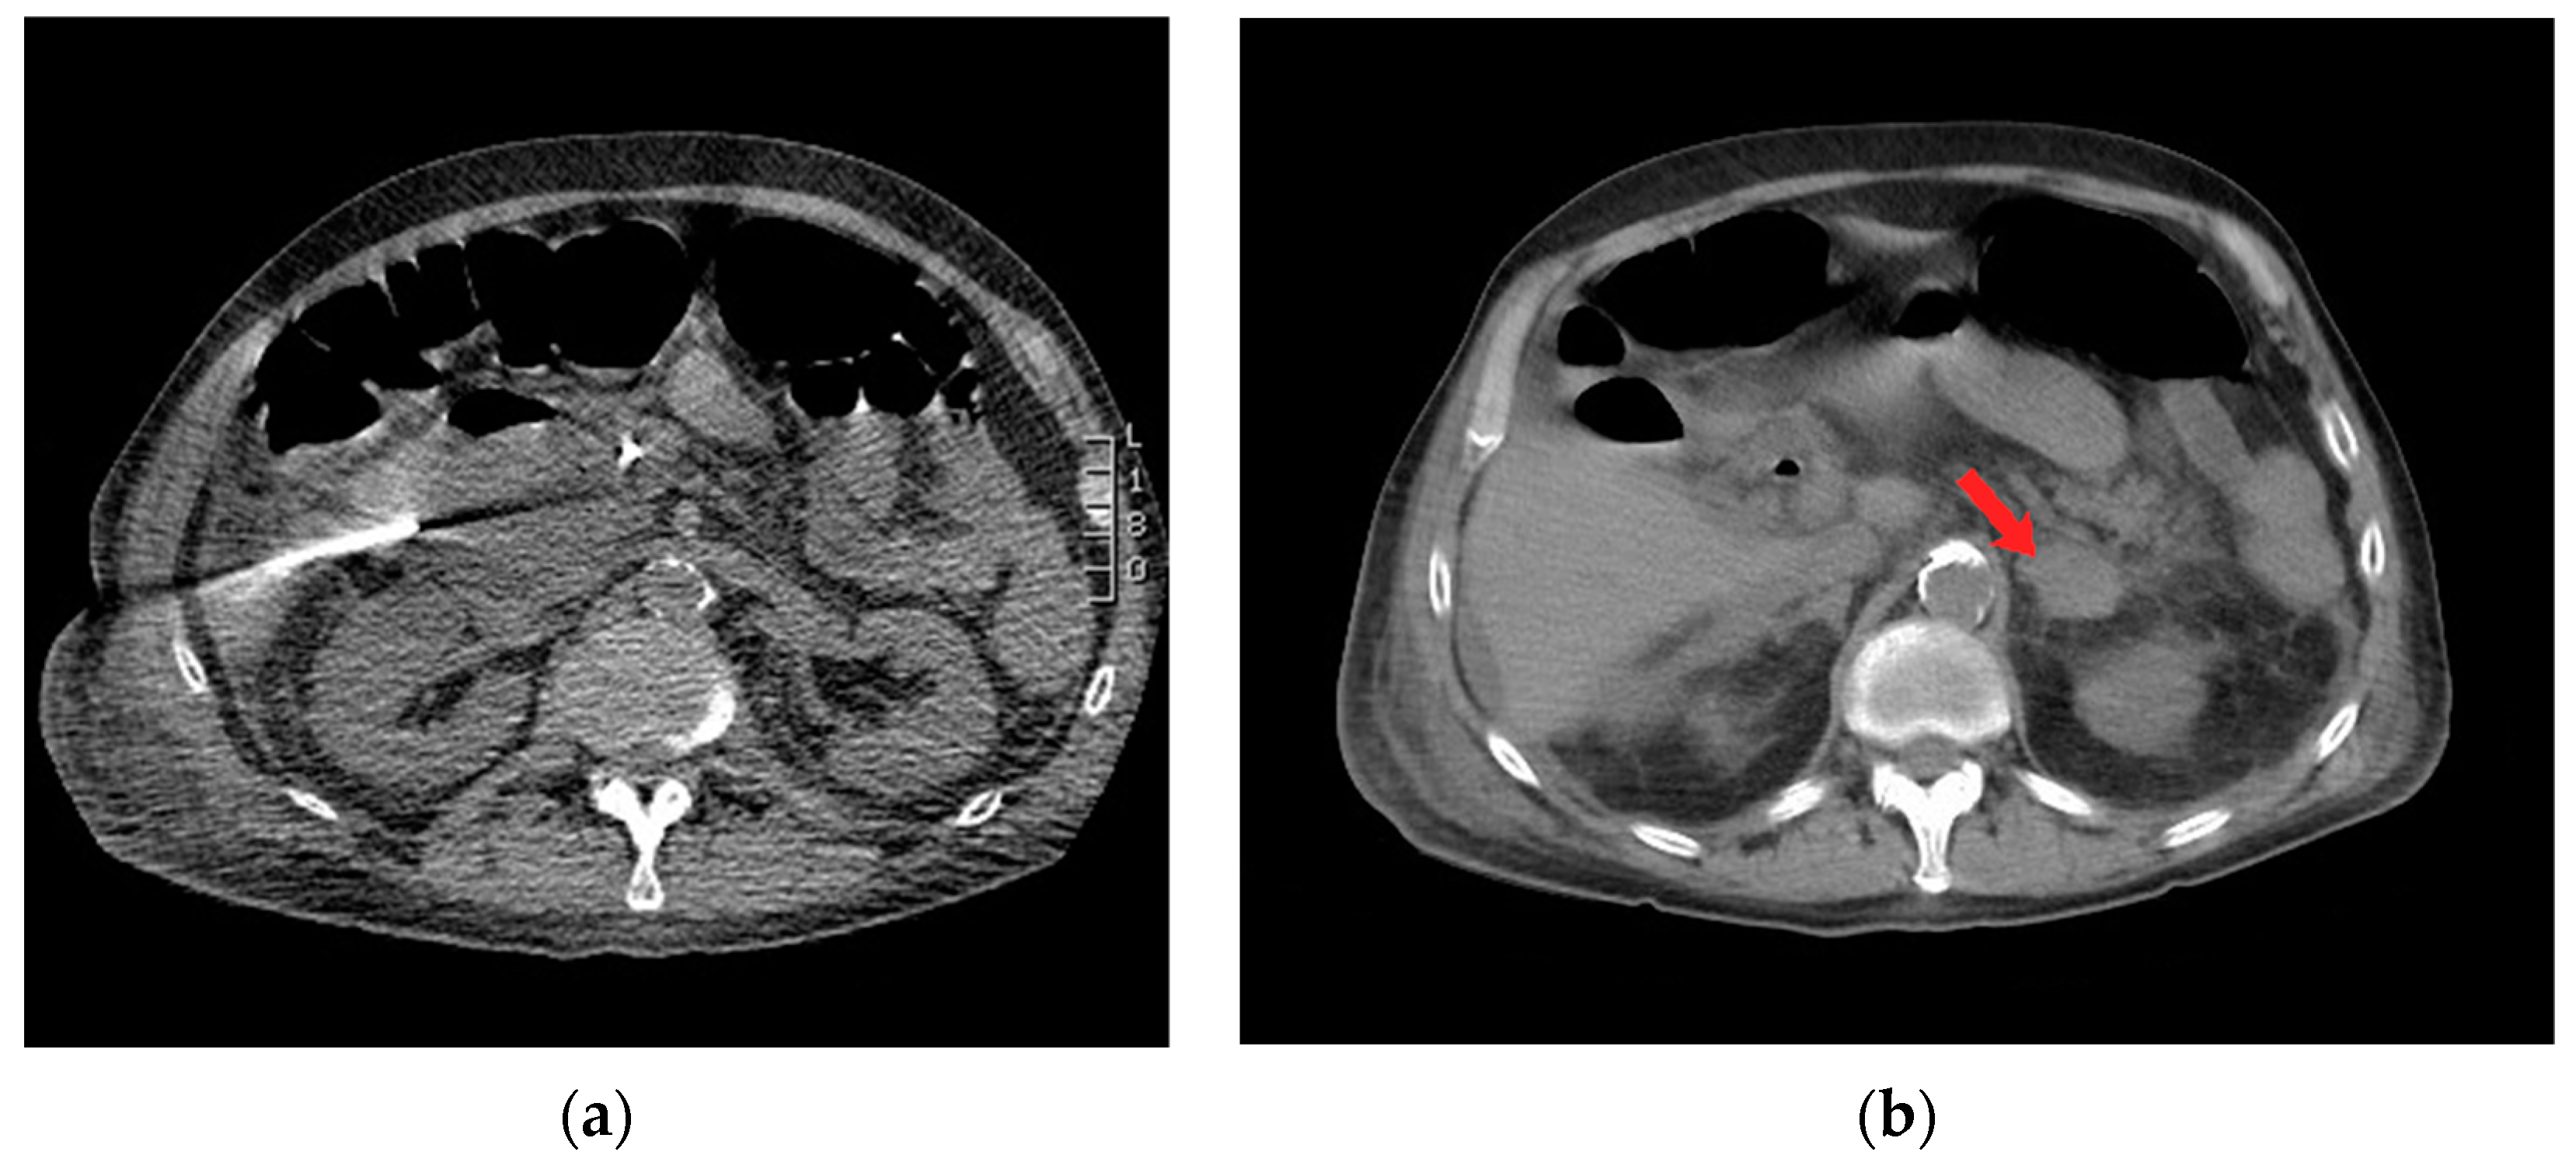

Figure 2.

Axial computed tomography (CT) imaging shows (a) percutaneous insertion of a 19 Gauge needle for drainage of periduodenal collection, and (b) left-sided adrenal hematoma with surrounding stranding of peri-adrenal fat (red arrow).

During the CT-guided drainage, after the needle punctured the collection and a wire was placed, the patient developed sudden onset left back pain and hypertension. CT imaging revealed a spontaneous left adrenal gland hemorrhage (Figure 2b). The drainage procedure was completed by inserting a 10 French drain over the wire and formed within the central aspect of the collection; turbid fluid was aspirated (Figure 3). After the procedure, the patient was observed in the CT suite. Intravenous (IV) analgesia was administered resulting in pain relief, and serial CT imaging with IV contrast showed stability of the left adrenal hemorrhage. Intravenous antihypertensives were administered to manage the acute hypertension. The patient was subsequently hospitalized for pain and hypertension management, secondary to spontaneous adrenal hemorrhage.